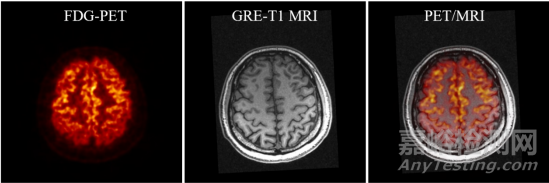

SIAT bPET和聯(lián)影uMR790 3T磁共振成像系統(tǒng)上同時(shí)獲得的人腦PET/MRI圖像

楊永峰介紹稱,與國外商業(yè)磁兼容腦PET成像儀器相比,SIAT bPET的效率提高了近2倍(從7.2%到14%),平均體分辨率提高了30倍以上(從約64mm3到2mm3)。同時(shí),SIAT bPET采用了創(chuàng)新的電子學(xué)和磁兼容設(shè)計(jì),使得磁共振成像對PET成像的影響幾乎可以忽略不計(jì),PET成像對磁共振成像圖像信噪比的影響小于5%,滿足同時(shí)開展PET/MRI成像的尖端科研需求。